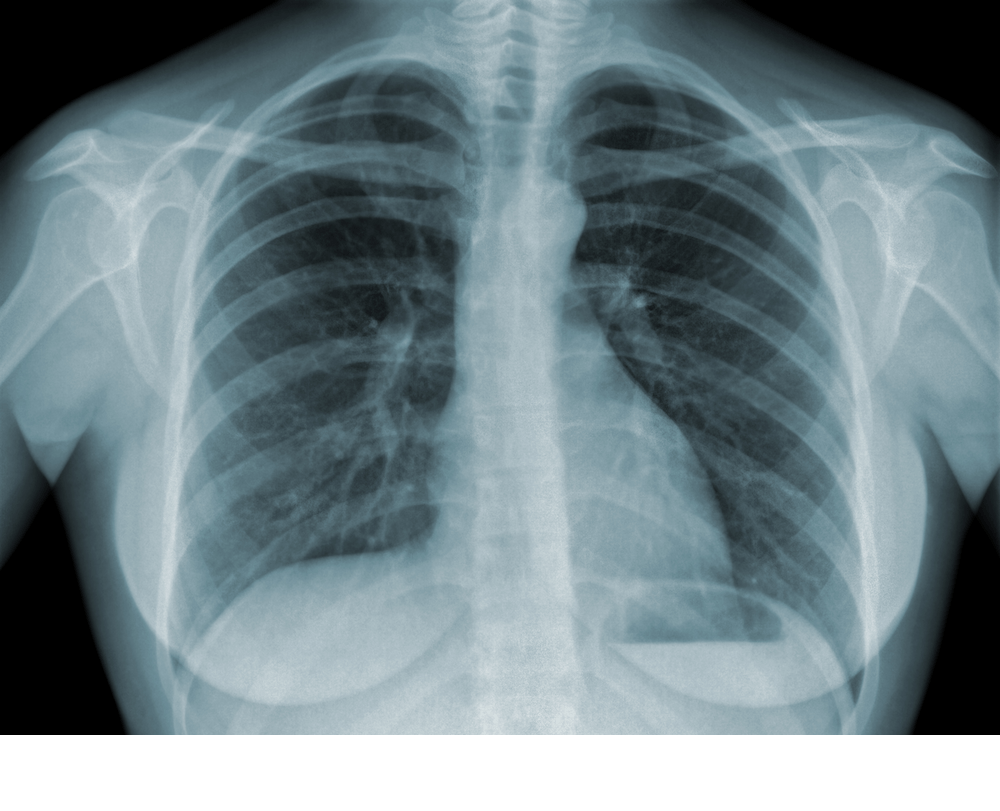

Il radon è un gas radioattivo generato da alcune rocce, principalmente laviche, pozzolane e granitiche. È un gas inerte, quindi non particolarmente dannoso nella sua forma originaria, ma purtroppo decade molto velocemente, trasformandosi in altri composti che, una volta inalati, continuano ad emettere raggi alfa (radioattivi) all'interno dei polmoni, danneggiando le cellule in maniera irreversibile. Per questa ragione, in Italia, il radon è considerato la seconda causa di tumore al polmone. La prima rimane il fumo di tabacco, che se combinata con l'esposizione al gas diventa ancora più pericolosa, aumentando il rischio fino al 50%.